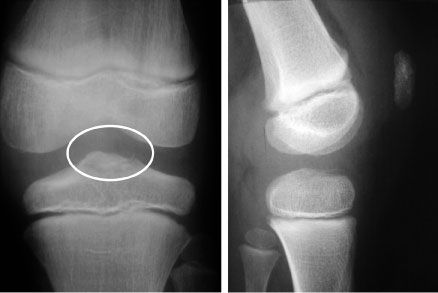

Mise au point Les lésions de la racine postérieure du ménisque interne , Guillaume Demey Lyon Ortho Clinic - Clinique de la Sauvegarde, 29B avenue des Sources, 69009 Lyon, France , Roger Badet Centre Ostéo Articulaire Fleming, 30 avenue Flemming, 38300 Bourgoin-Jallieu, France N°256 Cahier 2 - Août/Septembre 2016 ● 16 min de lecture